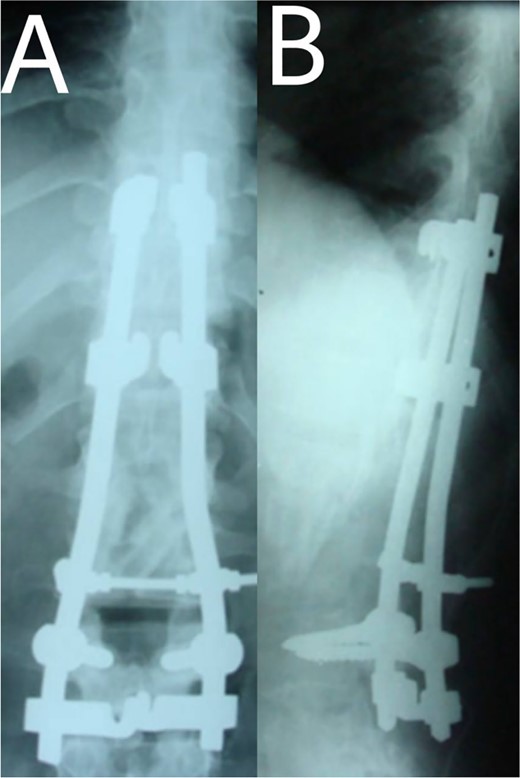

A 24-year-old farmer female was admitted to the Department of Neurosurgery with low back pain, no fever, cough, motor deficit, or any symptoms. Medical, surgical, family histories and physical examinations were unremarkable. The laboratory findings showed a white cell count of 9.8 × 103/μL, C-reactive protein concentrations of 20, erythrocyte sedimentation rate of 50 mm/1 h, 90 mm/2 h and tuberculin skin test was positive. X-ray films showed the collapse of the L1, L2 vertebrae, and L1–2 intervertebral space (Fig. 1). An abscess was observed at the L1–L2 vertebral level in lumbar magnetic resonance imaging (MRI) (Fig. 2). Chest X-rays and Sputum smear were negative. The patient was treated with anti-TB treatment (Isoniazid, Rifampicin, Ethambutol, Pyrazinamide) due to spinal TB findings on MRI (Fig. 3). After 40 days, the patient was diagnosed with grade 1/5 lower limb weakness, and bladder and bowel dysfunction, with no impairment in sensation, which predicts spinal infection. MRI confirmed these abnormalities and showed typical findings such as vertebral endplate destruction, bone marrow and disk signal abnormalities, and paravertebral or epidural abscesses (Fig. 3). Due to clinical manifestations and MRI spinal TB findings (Fig. 3), the patient underwent surgical debridement, interbody fusion and internal fixation with fibular autografting and supplemental posterior spinal stabilisation using a posterior-only approach. On post-operative follow-up, the treatment continued for 9 months, in addition to physical therapy for lower limb weakness. In the end, the patient returned to full motion with grade 5/5 in the lower limb, normal sensation, and no bladder or bowel incontinence. No recurrence was observed in the grafting area. Radiologically 2, 6 and 12 months, 14 years’ post-operation, the patient had achieved full bony graft spinal fusion (Figs 4–6).

(A, B) 2, 4 months after single-stage posterior extensive debridement and fibular autograft implantation followed by supplemental posterior instrumentation performed to treat the spinal infection.